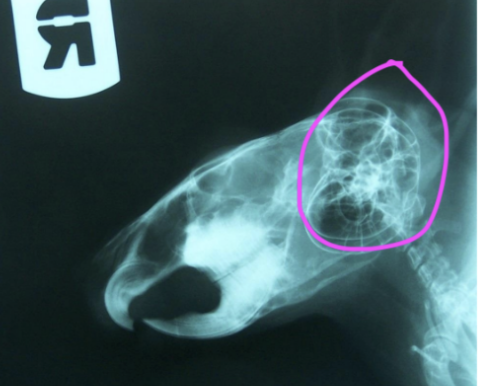

Rabbit right maxillary dentition

101-102 (incisors)

(no canines)

106-108 (premolars)

109-111 (molars)

4 views minimum for small mammal dental X rays

Lateral

2x lateral oblique

Dorsoventral

(rostrocaudal)